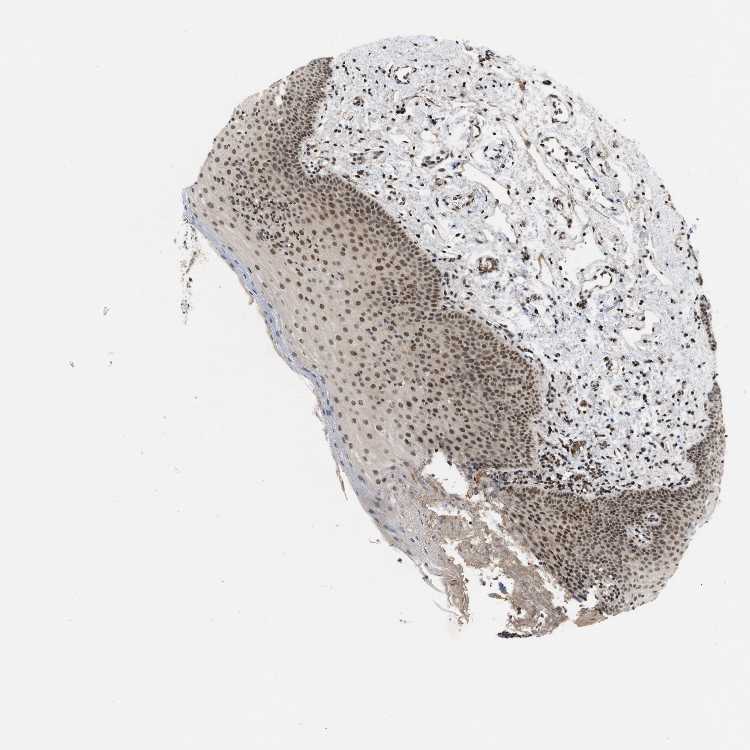

TISSUE PRIMARY DATA ORAL MUCOSA Show tissue menu

ORAL MUCOSA - Antibody stainingi

Antibody staining in the annotated cell types in the current human tissue is reported as not detected, low, medium, or high, based on conventional immunohistochemistry profiling in selected tissues. This score is based on the combination of the staining intensity and fraction of stained cells.

Each image is clickable and will lead to virtual microscopy that enables deeper exploration of all samples and also displays staining intensity scores, fraction scores and subcellular localization as well as patient and tissue information for each sample.

Antibody HPA018485

Squamous epithelial cells Medium